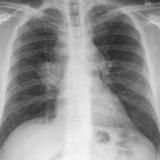

Gallery Lung Cancer

Lung Cancer